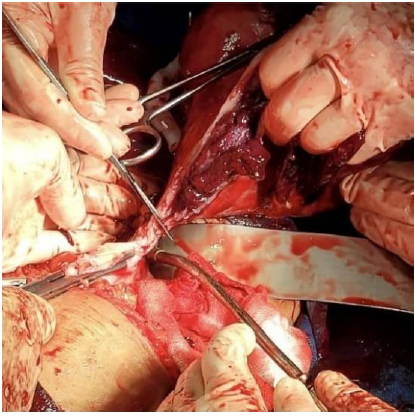

An anomaly scan was done at 18 weeks and was found to be normal. However, ultrasound findings were consistent with total placenta previa and features suggestive of placenta percreta, including bridging vessels and multiple placental lakes (Figure 1). Despite repeated counseling regarding the risks, including hemorrhage, maternal and fetal mortality, peripartum hysterectomy, and extensive blood product transfusion, the patient chose to continue the pregnancy.

Figure 1. Ultrasonographic image at 18 weeks of gestation showing a complete placenta previa with thinning of the myometrium between the placenta and the bladder, indicating placenta previa